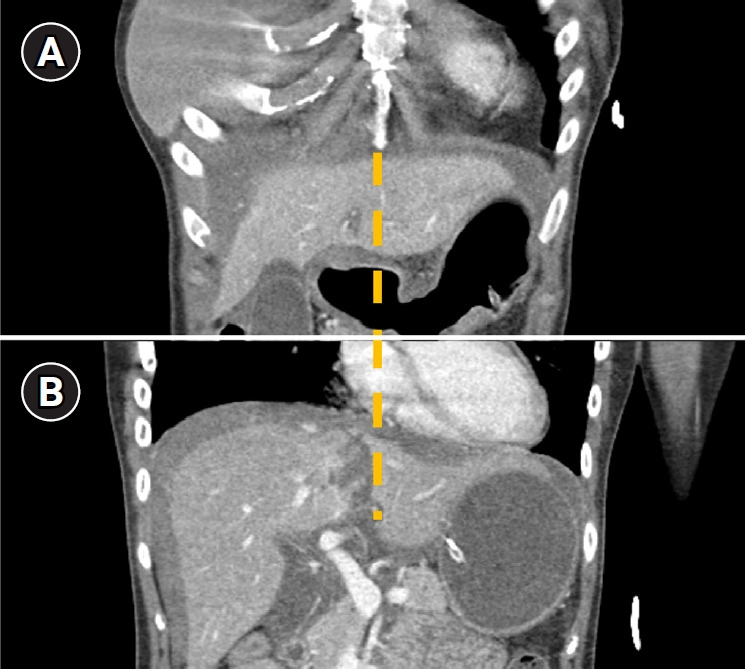

Cardiac compression is the most crucial component of successful cardiopulmonary resuscitation (CPR). However, CPR procedure poses a risk of complications, even when CPR providers perform cardiac compressions as recommended. Reports indicate that solid organ injuries, including liver injuries, occur with an incidence of about 0.6% to 3%. In this particular case, a 25-year-old woman was found hanged in her apartment. She was transported to a nearby hospital where CPR was administered for approximately 30 minutes until she was resuscitated. Subsequently, an abdomen-pelvis computed tomography scan revealed a liver injury. The location of the liver injury, between the sternum and spine, suggested it was a compression injury caused by CPR. There was no evidence of extravasation or active bleeding; thus, conservative management was chosen for the liver injury. By hospital day 4, the patient's pupil reflex had completely disappeared. Electroencephalography showed generalized attenuation, indicating severe global brain damage. Liver injury is a relatively rare post-CPR complication, with an incidence of 0.6% according to a retrospective analysis of a cardiac arrest registry. The liver is partially situated between the sternum and spine. The end of the sternum is shaped like an inverted triangle, resembling a sword. Therefore, if the CPR provider's hands are placed too low or excessive pressure is applied, the sternum can injure the left liver. Blood loss from liver injuries could potentially hinder the successful resuscitation of patients. In this case, had there been no blood loss from the liver injury, the patient might have maintained better cerebral perfusion and function.